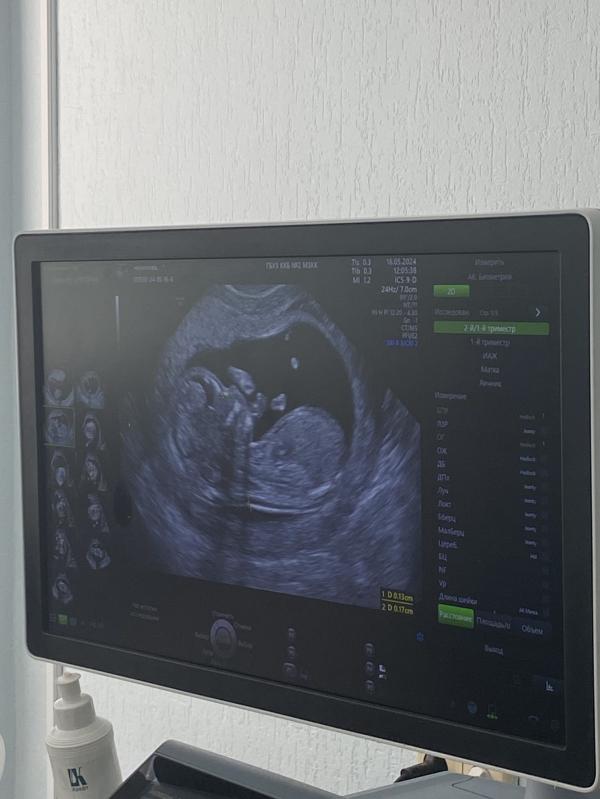

Боже мой, девочки это самое сложное ожидание, эти две недели со скрининга тянулись ужасно долго. Но слава богу закончились, в общем в платной мне сказали нет даже смысла смотреть так как они это не увидят, я ждала 30 мая(сегодня) чтоб попасть к генетикам, было узи и консультация, узи специалист Кариди А В. Очень хорошая осторожная, тактичная девушка, все посмотрела и доступным языком объяснила, затем направили к Лашевич Полине генетик в мгк, и собственно лучшие специалисты сказали что прогнозы хорошие, подтвердили крестцово копчиковую тератому, опухоль доброкачественная, и в дальнейшем операбельная, у нас в городе в краевой детской делают такого рода операции деткам, так что я приняла решение что буду оставлять свою кроху,в 20 недель узи в мгк, будут оценивать масштабы опухоли и как она себя ведет, вы просто не представляете как я была Рада слышать хорошие новости, расплакалась от счастья, прям гора с плеч…. Хочу сказать что я облазила все что можно и нашла много информации про наш диагноз, и в большинстве случаев все очень хорошо заканчивается, буду делиться тут всем что буду узнавать, чтоб девочки которым ставят этот диагноз знали что шансы есть